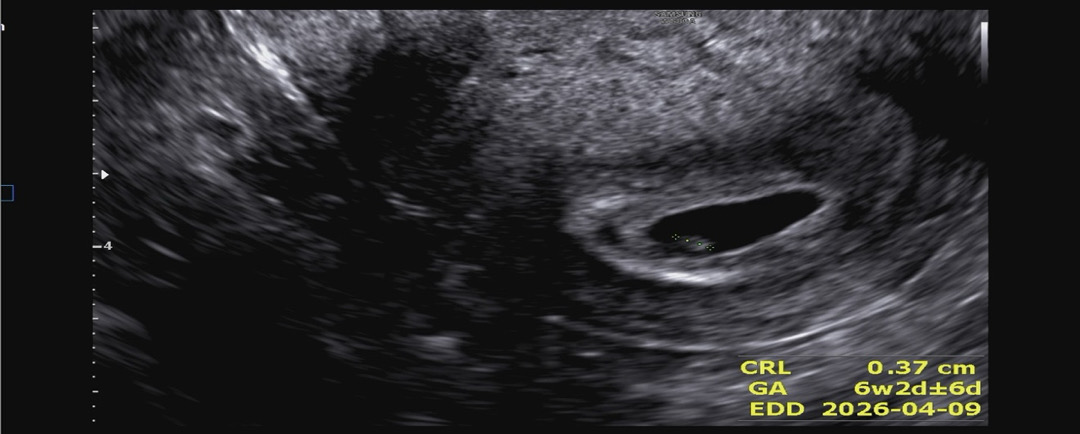

임신 6주차

6주2일이구 출산 예정일은 4월7일이야 오늘 낮에 출산병원 가서 산모수첩하고 난황이랑 애기로 추정되는거까지 보고왔당! 근데 심장소리는 못들어서 많이 아쉬웠어ㅠㅠ주수에 맞게 잘 크고 있는건지도 궁금하구.. 근데 여기 엄마들중에 임신 초기에 손 다리 붓기 심하거나 심했던 엄마들 있어?ㅠㅠ 아까 남편이랑 진료 갔다가 닭갈비먹구 좀비딸 보고 니왔는데 심할정도로 부어서 걱정이 이만저만이 아니당..